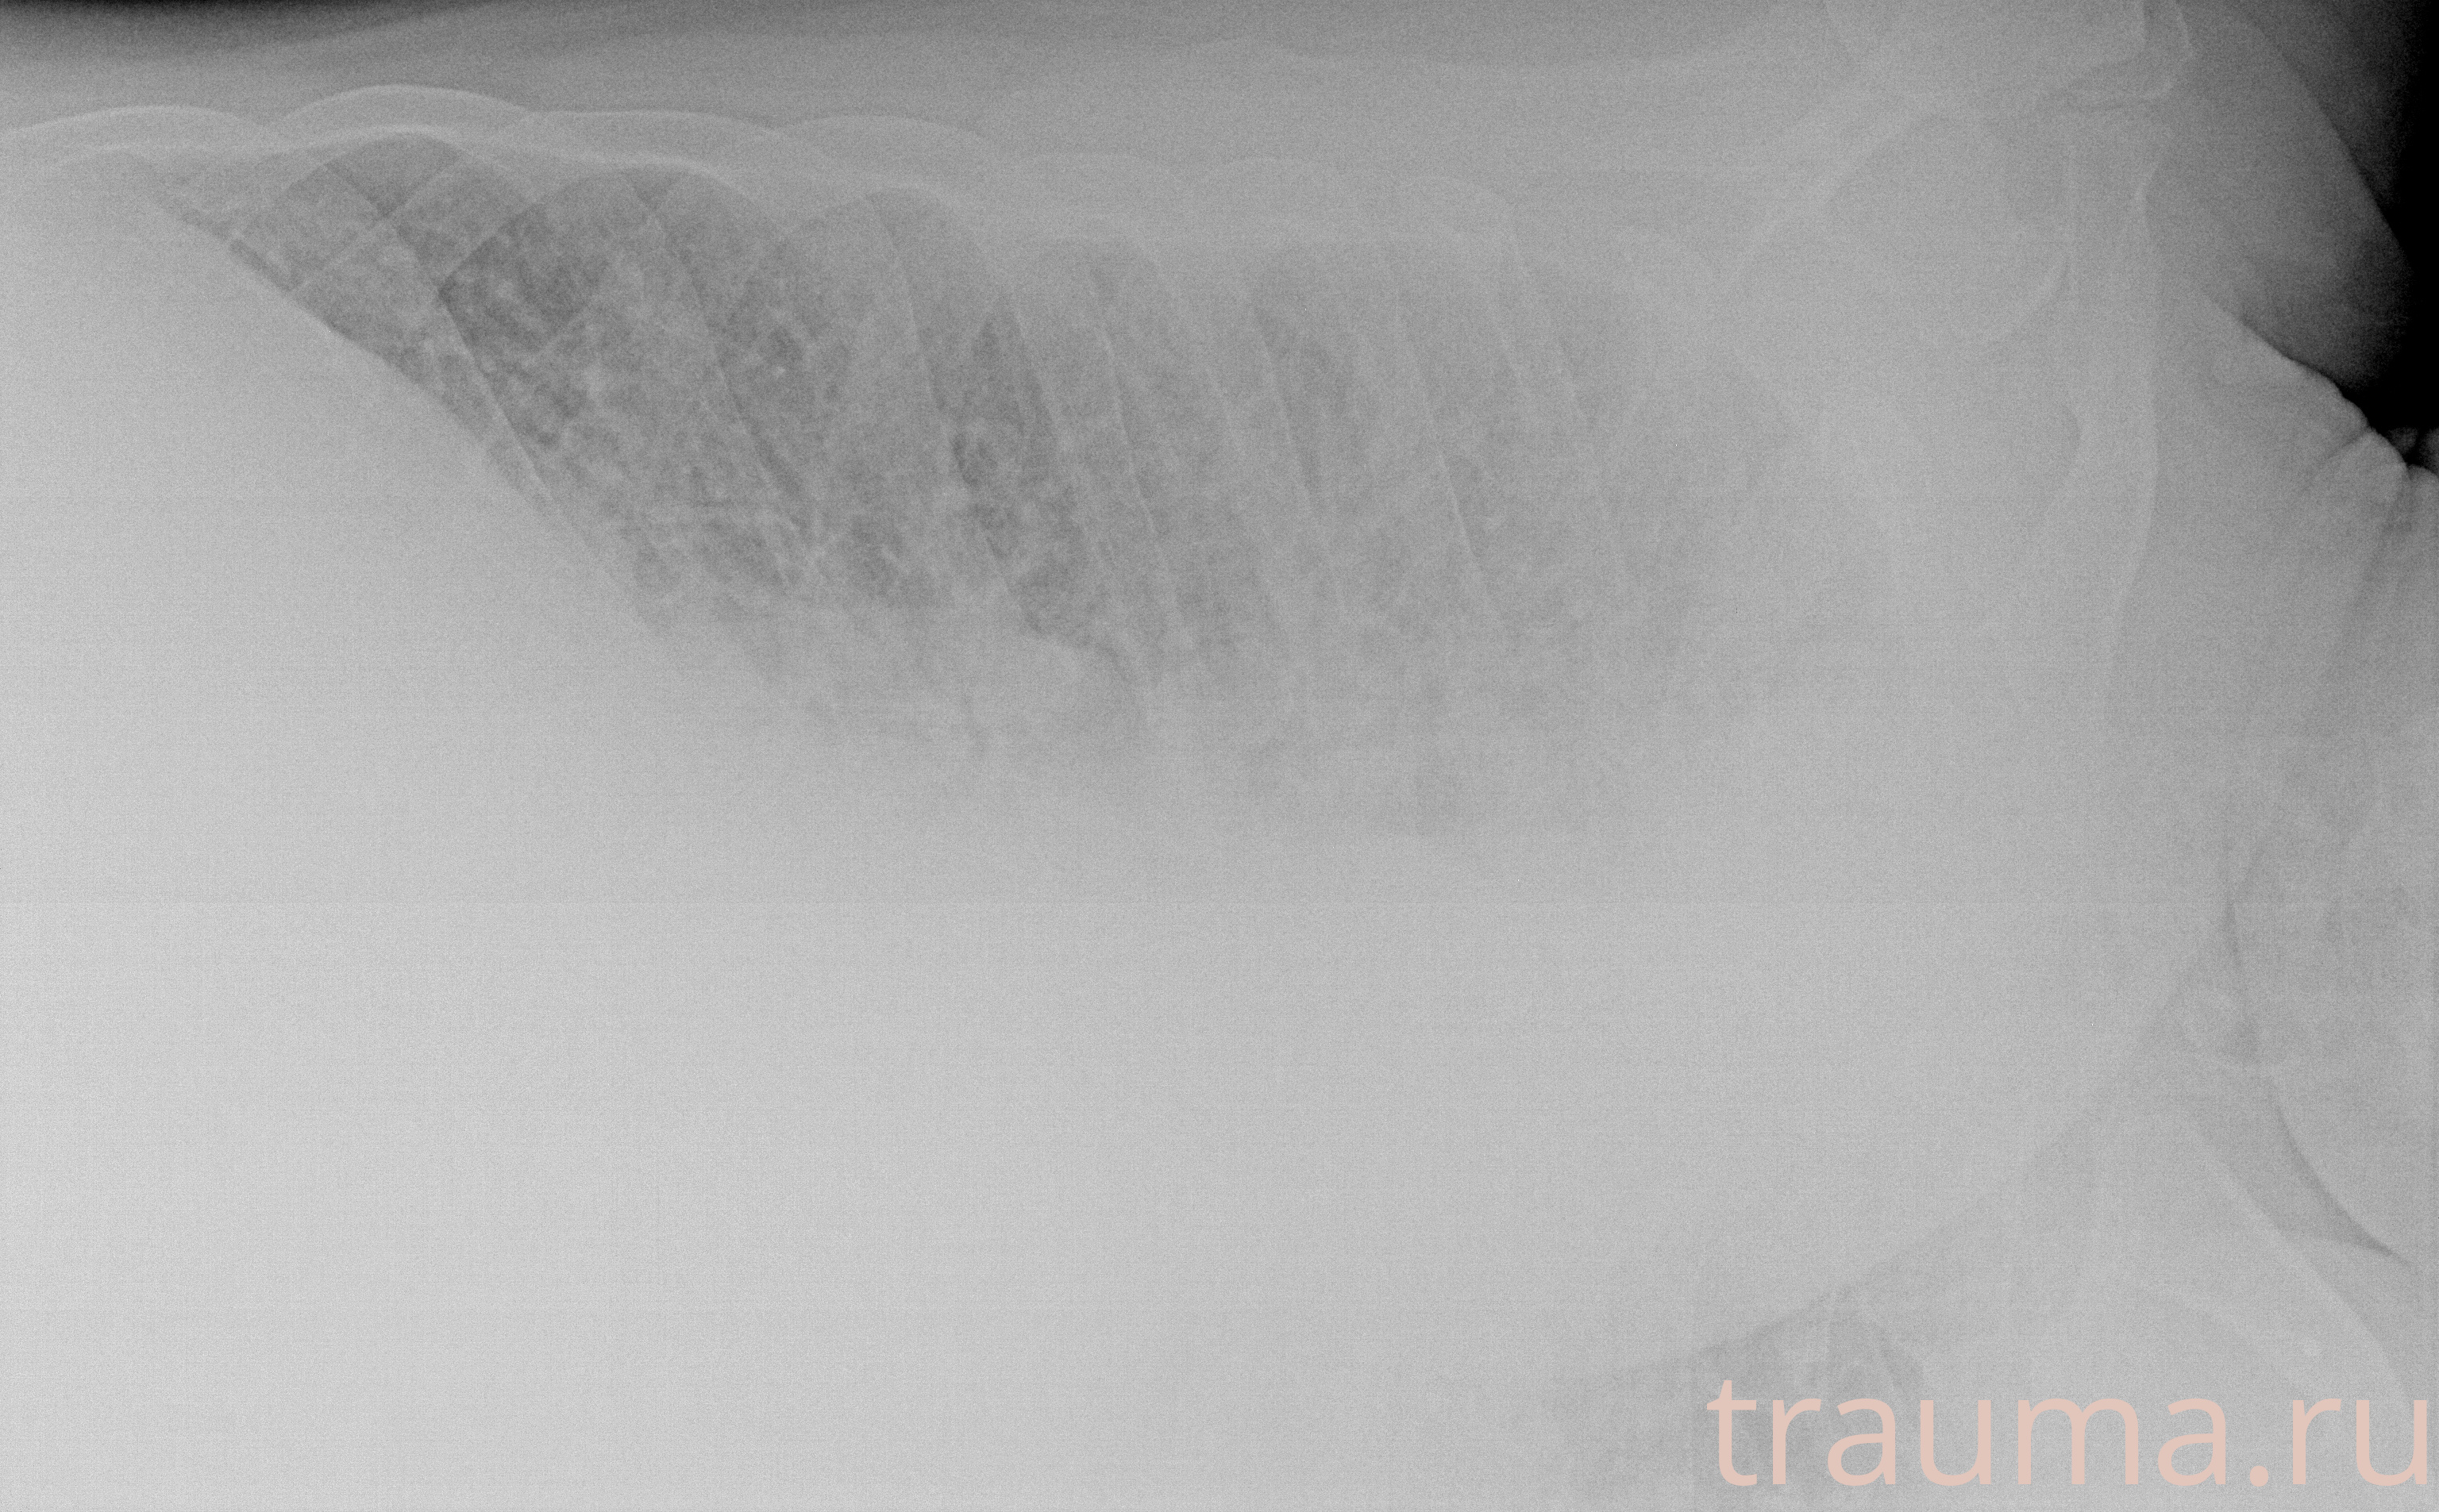

Рентген на дому: по вашему адресу приезжает врач-рентгенолог, травматолог-ортопед с мобильным рентгеновским аппаратом, проводит диагностику травмы или заболевания, делает необходимые рентгенограммы, дает рекомендации по дальнейшему лечению. Получить качественные снимки в домашних условиях возможно благодаря уникальной методике, разработанной МосРентген Центром для института  Склифосовского